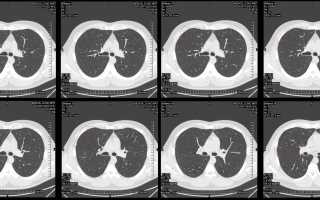

Компьютерная томография органов грудной клетки

Процесс проведения КТ начинается с беседы, в ходе которой врач объясняет пациенту все нюансы исследования. Пациент располагается на специальном подвижном столе, к которому его фиксируют ремнями. При необходимости выполняется внутривенное введение контрастного вещества. Затем осуществляется облучение грудной клетки ионизирующим излучением, в результате чего формируются срезы. На основе этих срезов создается трехмерное изображение, которое сохраняется или записывается на пленку. По завершении процедуры пациенту рекомендуется пить много жидкости для быстрого выведения контрастного вещества из организма.